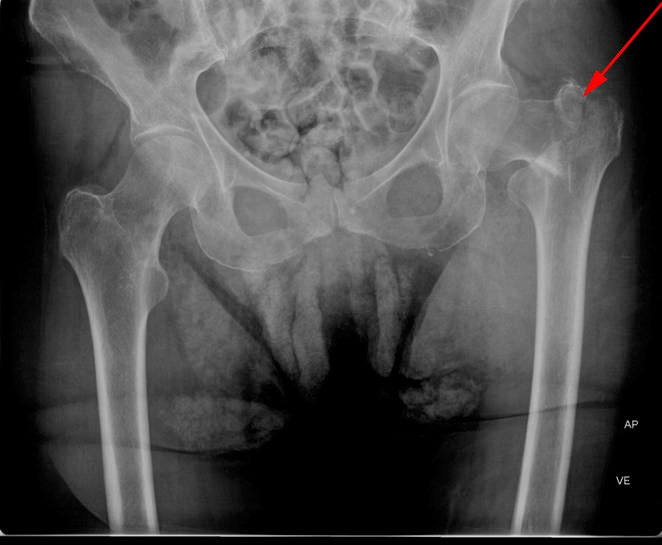

Røntgenbillede af begge hofter forfra (øverst) og enkelt billede af venstre hofte fra siden viser et brud gennem øverste del af lårbensknoglen (rød pil), kaldet hoftebrud.